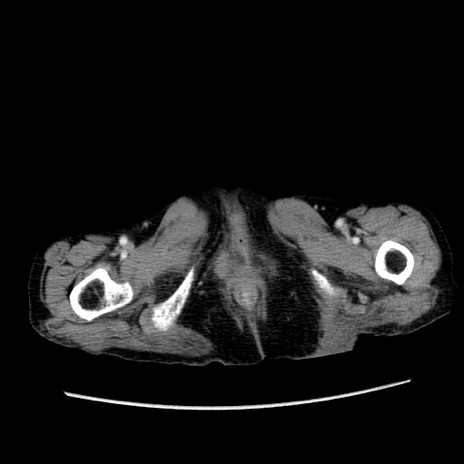

冠状断像

【症例】80歳代女性

【主訴】胸のつかえ感

【現病歴】約9時間前に食後から胸のつかえた感じあり、嘔吐あり、来院。

【既往歴】胃癌(全摘)、胆摘、虫垂炎

【身体所見】心窩部に圧痛あり、反跳痛なし。

【データ】WBC 5700、CRP 0.05